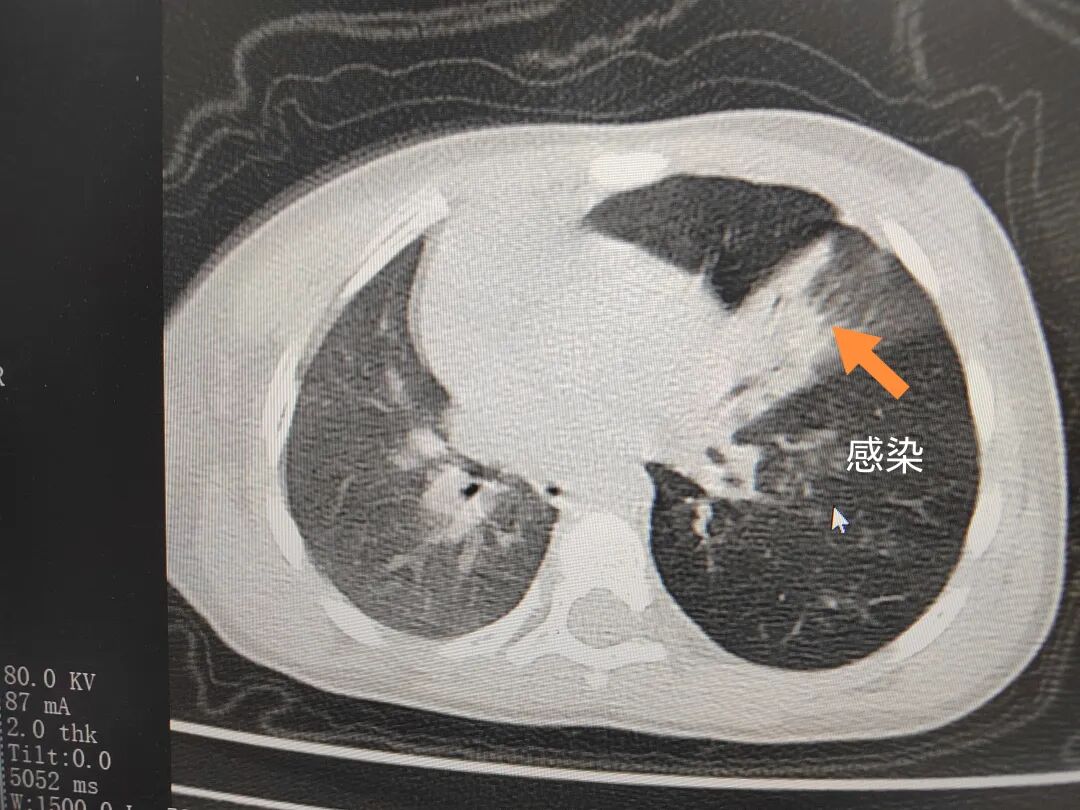

三天后(11月13日),趙寶出現高熱、咳喘加重,家長著急了,再次帶他來到醫(yī)院。CT檢查顯示左肺過度充氣,左肺上下葉支氣管主干見不規(guī)則高密度影,左肺上葉可見大片狀密度增高影,縱隔窗實變,提示為“左側支氣管內異物并繼發(fā)性改變,左肺上葉舌段肺膨脹不全”。